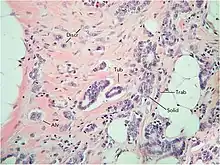

Despite the structural diversity of the primary breast tumor, five main types of morphological structures can be distinguished: alveolar, trabecular, tubular and solid structures, and discrete groups of tumor cells. The alveolar structures are tumor cell clusters of round or slightly irregular shape. The morphology of the cells that form this type of structures varies from small cells with moderate cytoplasm and round nuclei to large cells with hyperchromatic nuclei of irregular shape and moderate cytoplasm. The trabecular structures are either short, linear associations formed by a single row of small, rather monomorphic cells or wide cell clusters consisting of two rows of medium-sized cells with moderate cytoplasm and round normochromic or hyperchromatic nuclei. The tubular structures are formed by a single or two rows of rather monomorphic cells with round normochromic nuclei. The solid structures are fields of various sizes and shapes, consisting of either small cells with moderate cytoplasm and monomorphic nuclei or large cells with abundant cytoplasm and polymorphic nuclei. Discrete groups of cells occur in the form of clusters of one to four cells with variable morphologies.[2]

The different morphological structures of breast tumors correspond to certain types of invasion. Therefore, alveolar, trabecular, and solid structures that are characterized by the presence of cell-cell contacts may be referred to morphological manifestations of collective migration, while discrete groups of tumor cells may be referred to manifestations of individual migration. The first batch of data obtained in a study of the expression of cell adhesion genes confirms this hypothesis. For example, there was a decrease in the activity of the genes of cadherins, which are responsible for cell-cell contacts, in the order: solid – alveolar and trabecular structures – discrete groups of tumor cells. In this case, the number of expressed genes of integrins involved in the adhesion of tumor cells to the extracellular matrix was reduced in the order: solid and alveolar – trabecular structures – discrete groups of tumor cells.[2]